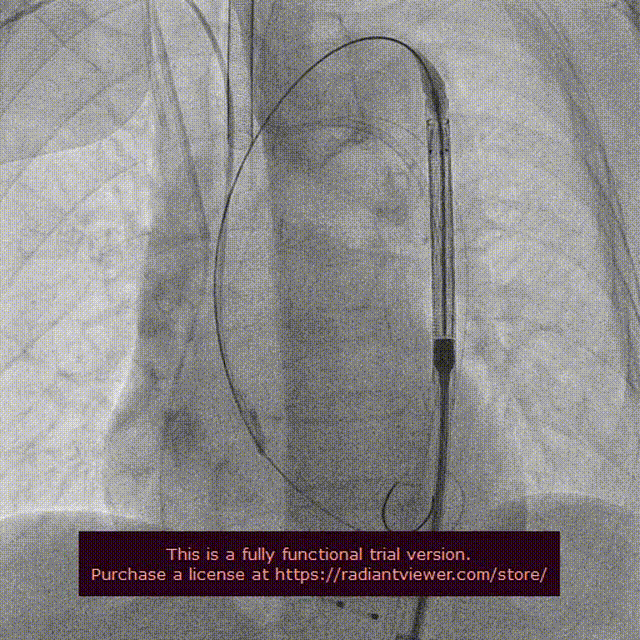

瓣膜定位释放

瓣膜释放过程

瓣膜完整形态

在影像、超声的共同指引下,术者团队通过调整输送系统至最佳位置实现精准释放,患者跨瓣压差即刻显著下降至0mmhg。再行主动脉造影提示瓣膜置入位置良好、形态完整,超声提示未见明显瓣周漏。术中及术后未出现相关并发症,圆满取得此次手术成功。